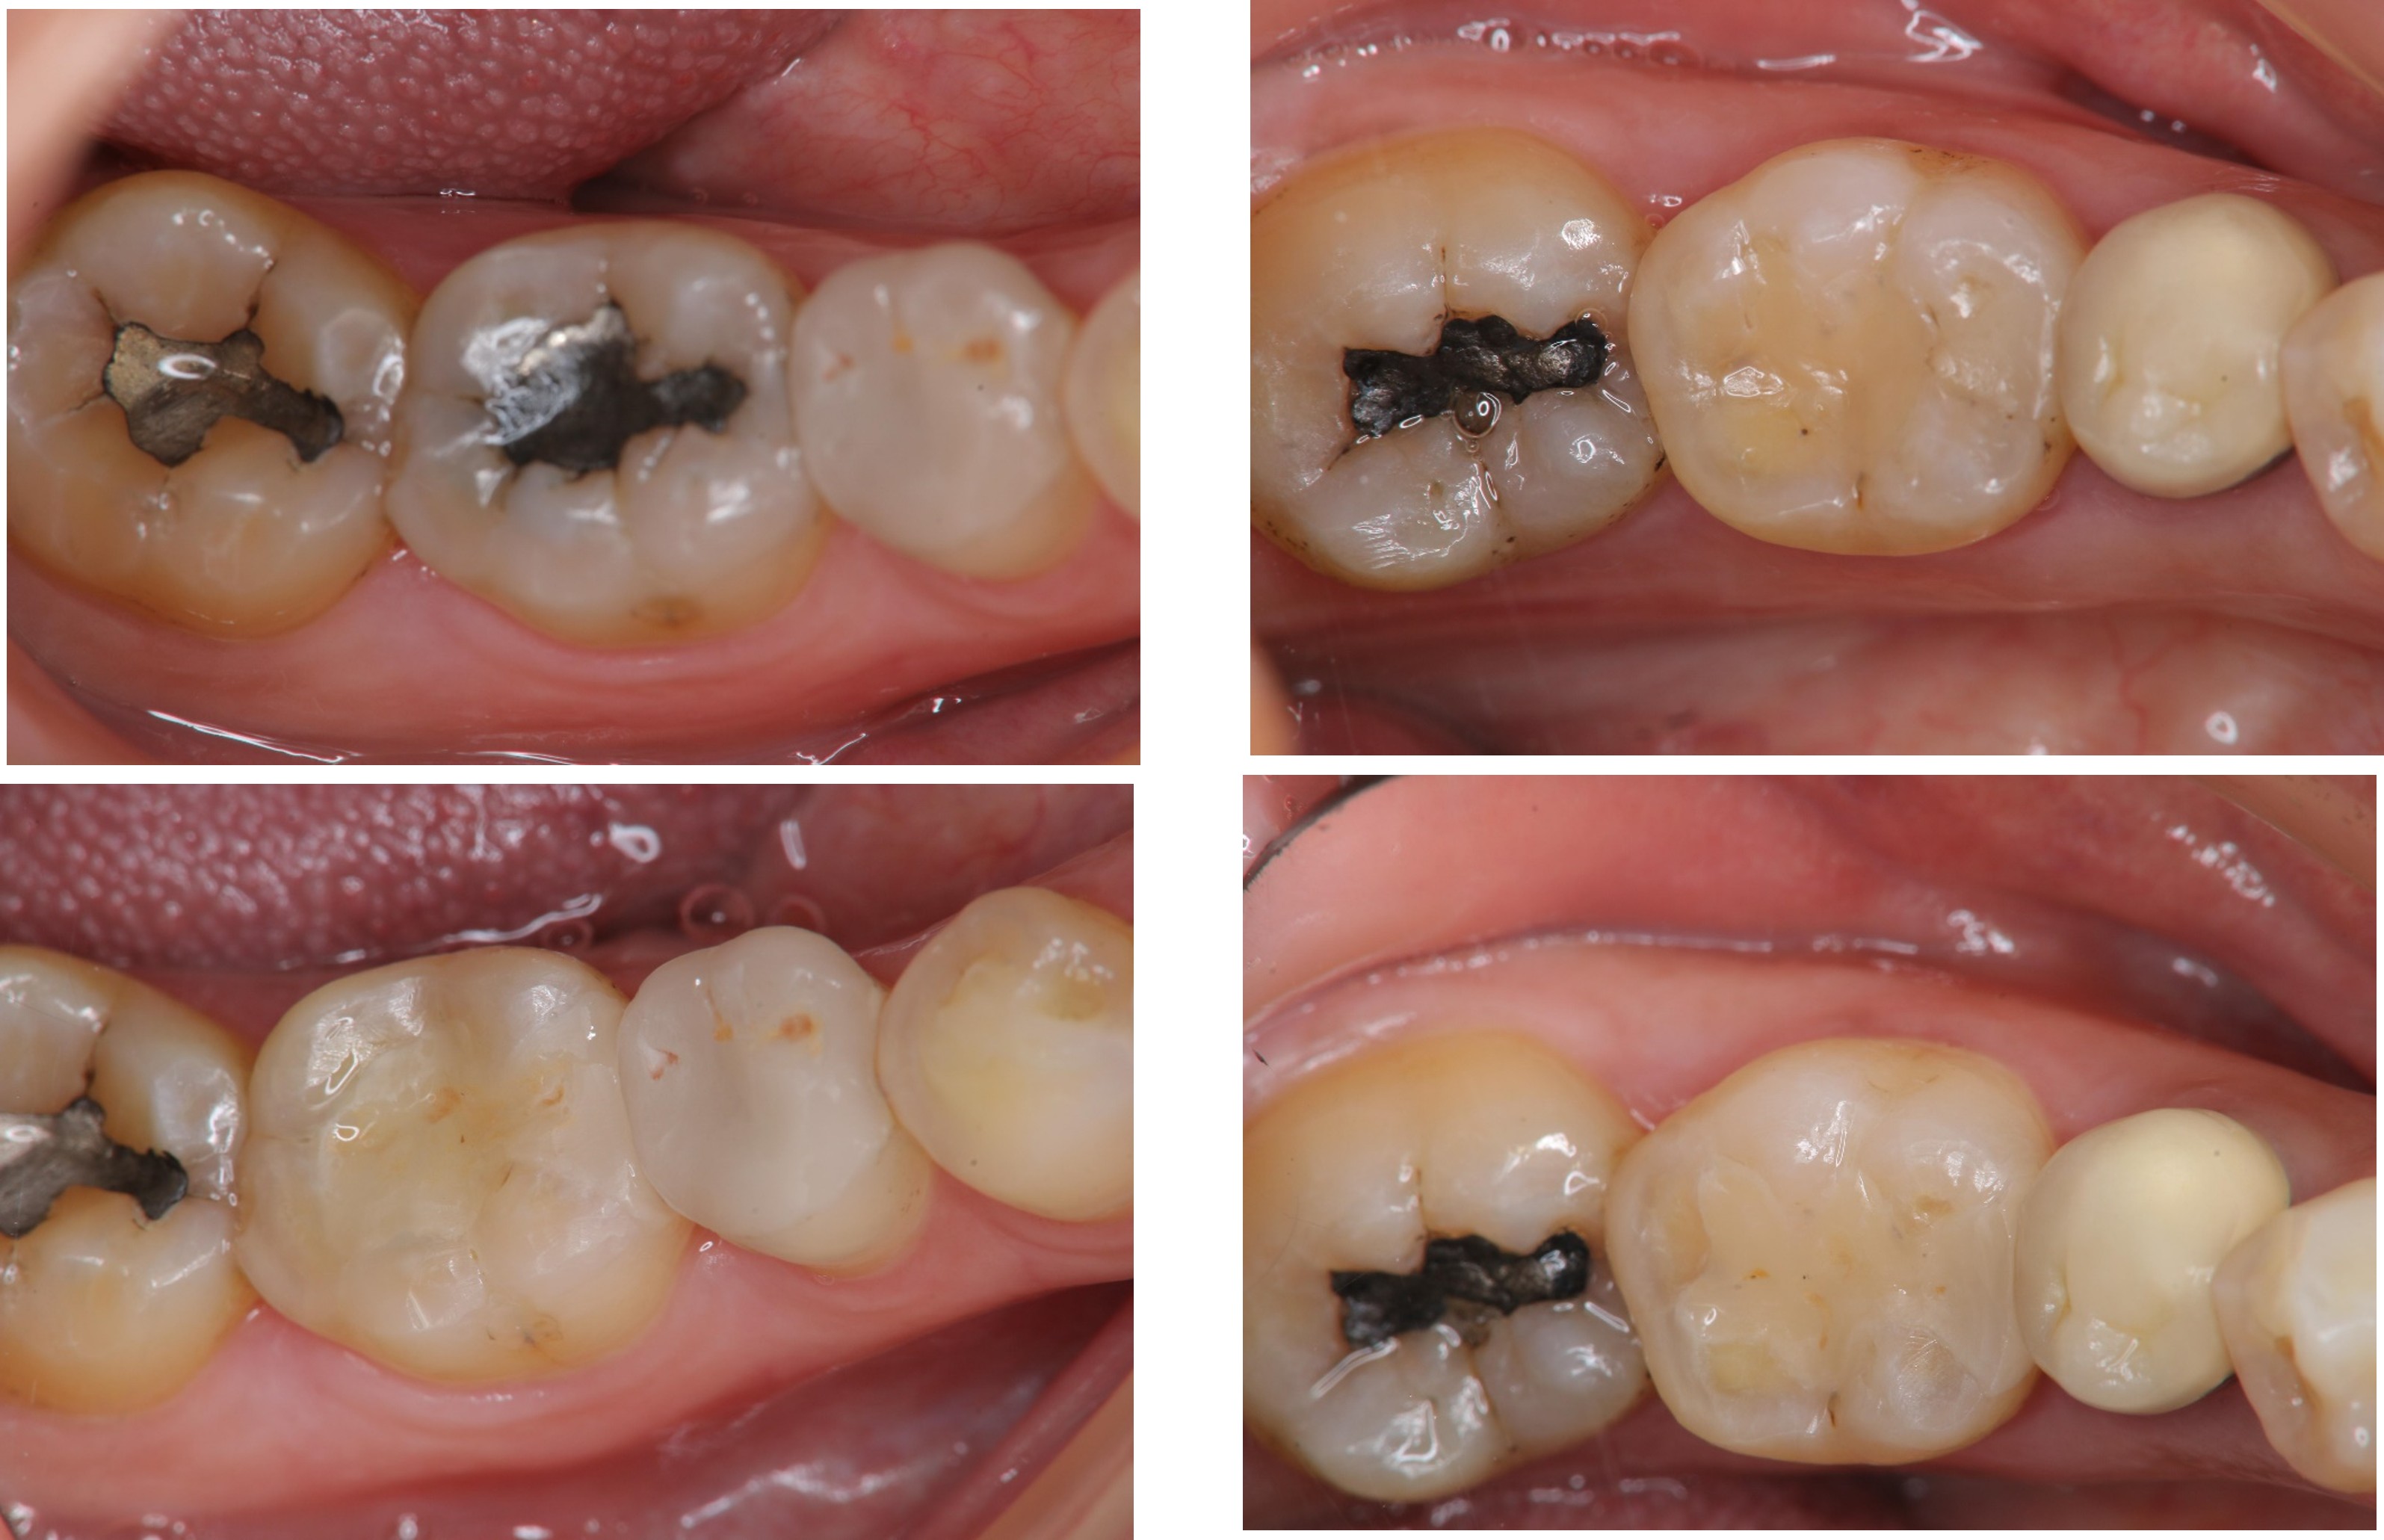

治療前,大臼齒冷熱敏感

術前、術後比較